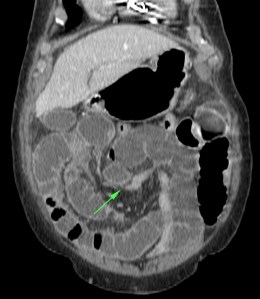

Se realiza TC de abdomen en vacío y con contraste en fase portal:

Estamos ante un cuadro de isquemia intestinal en un paciente con bajo gasto cardiaco con afectación principal de asas intestino delgado, territorio vacularizado por la arteria mesentérica superior.